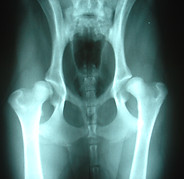

At FoxFire, our personal dogs have their hips X-rayed and evaluated by the Orthopedic Foundation for Animals (OFA), cardiac testing performed and cleared by a board-certified cardiologist through OFA, and eye certifications completed through OFA as well. Each of these clearances requires specialized testing and represents a significant investment often costing far more than a standard veterinary exam.

Beagled selected for breeding have OFA cleared heart, hips and eyes